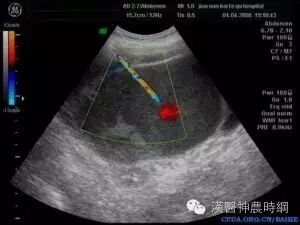

B超声象图:B超显象是目前辅助诊断子宫内膜异位症的有效方法,主要用以观察卵巢子宫内膜异位囊肿,其声象图的特征为:囊性肿块,边界清晰或不清。如囊肿周围粘连重,则边界不清;如囊肿与子宫或周围组织粘连少,则边界清晰。囊肿多为中等大小,囊肿内可见颗粒状细小回声,是囊液粘稠表现。有时因陈旧性血块浓缩机化而出现较密集的粗光点图象,呈混合性肿块状。

肿块常位于子宫后侧,可见囊肿子宫伴随症。囊肿自发破裂时,声象图示后凹陷,囊肿较前缩小。腹腔镜检查:腹腔镜检查是目前诊断子宫内膜异位症的新标准,通过腹腔镜可直接窥视盆腔,见到异位病灶即可明确诊断,且可进行临床分期,以决定治疗方案。